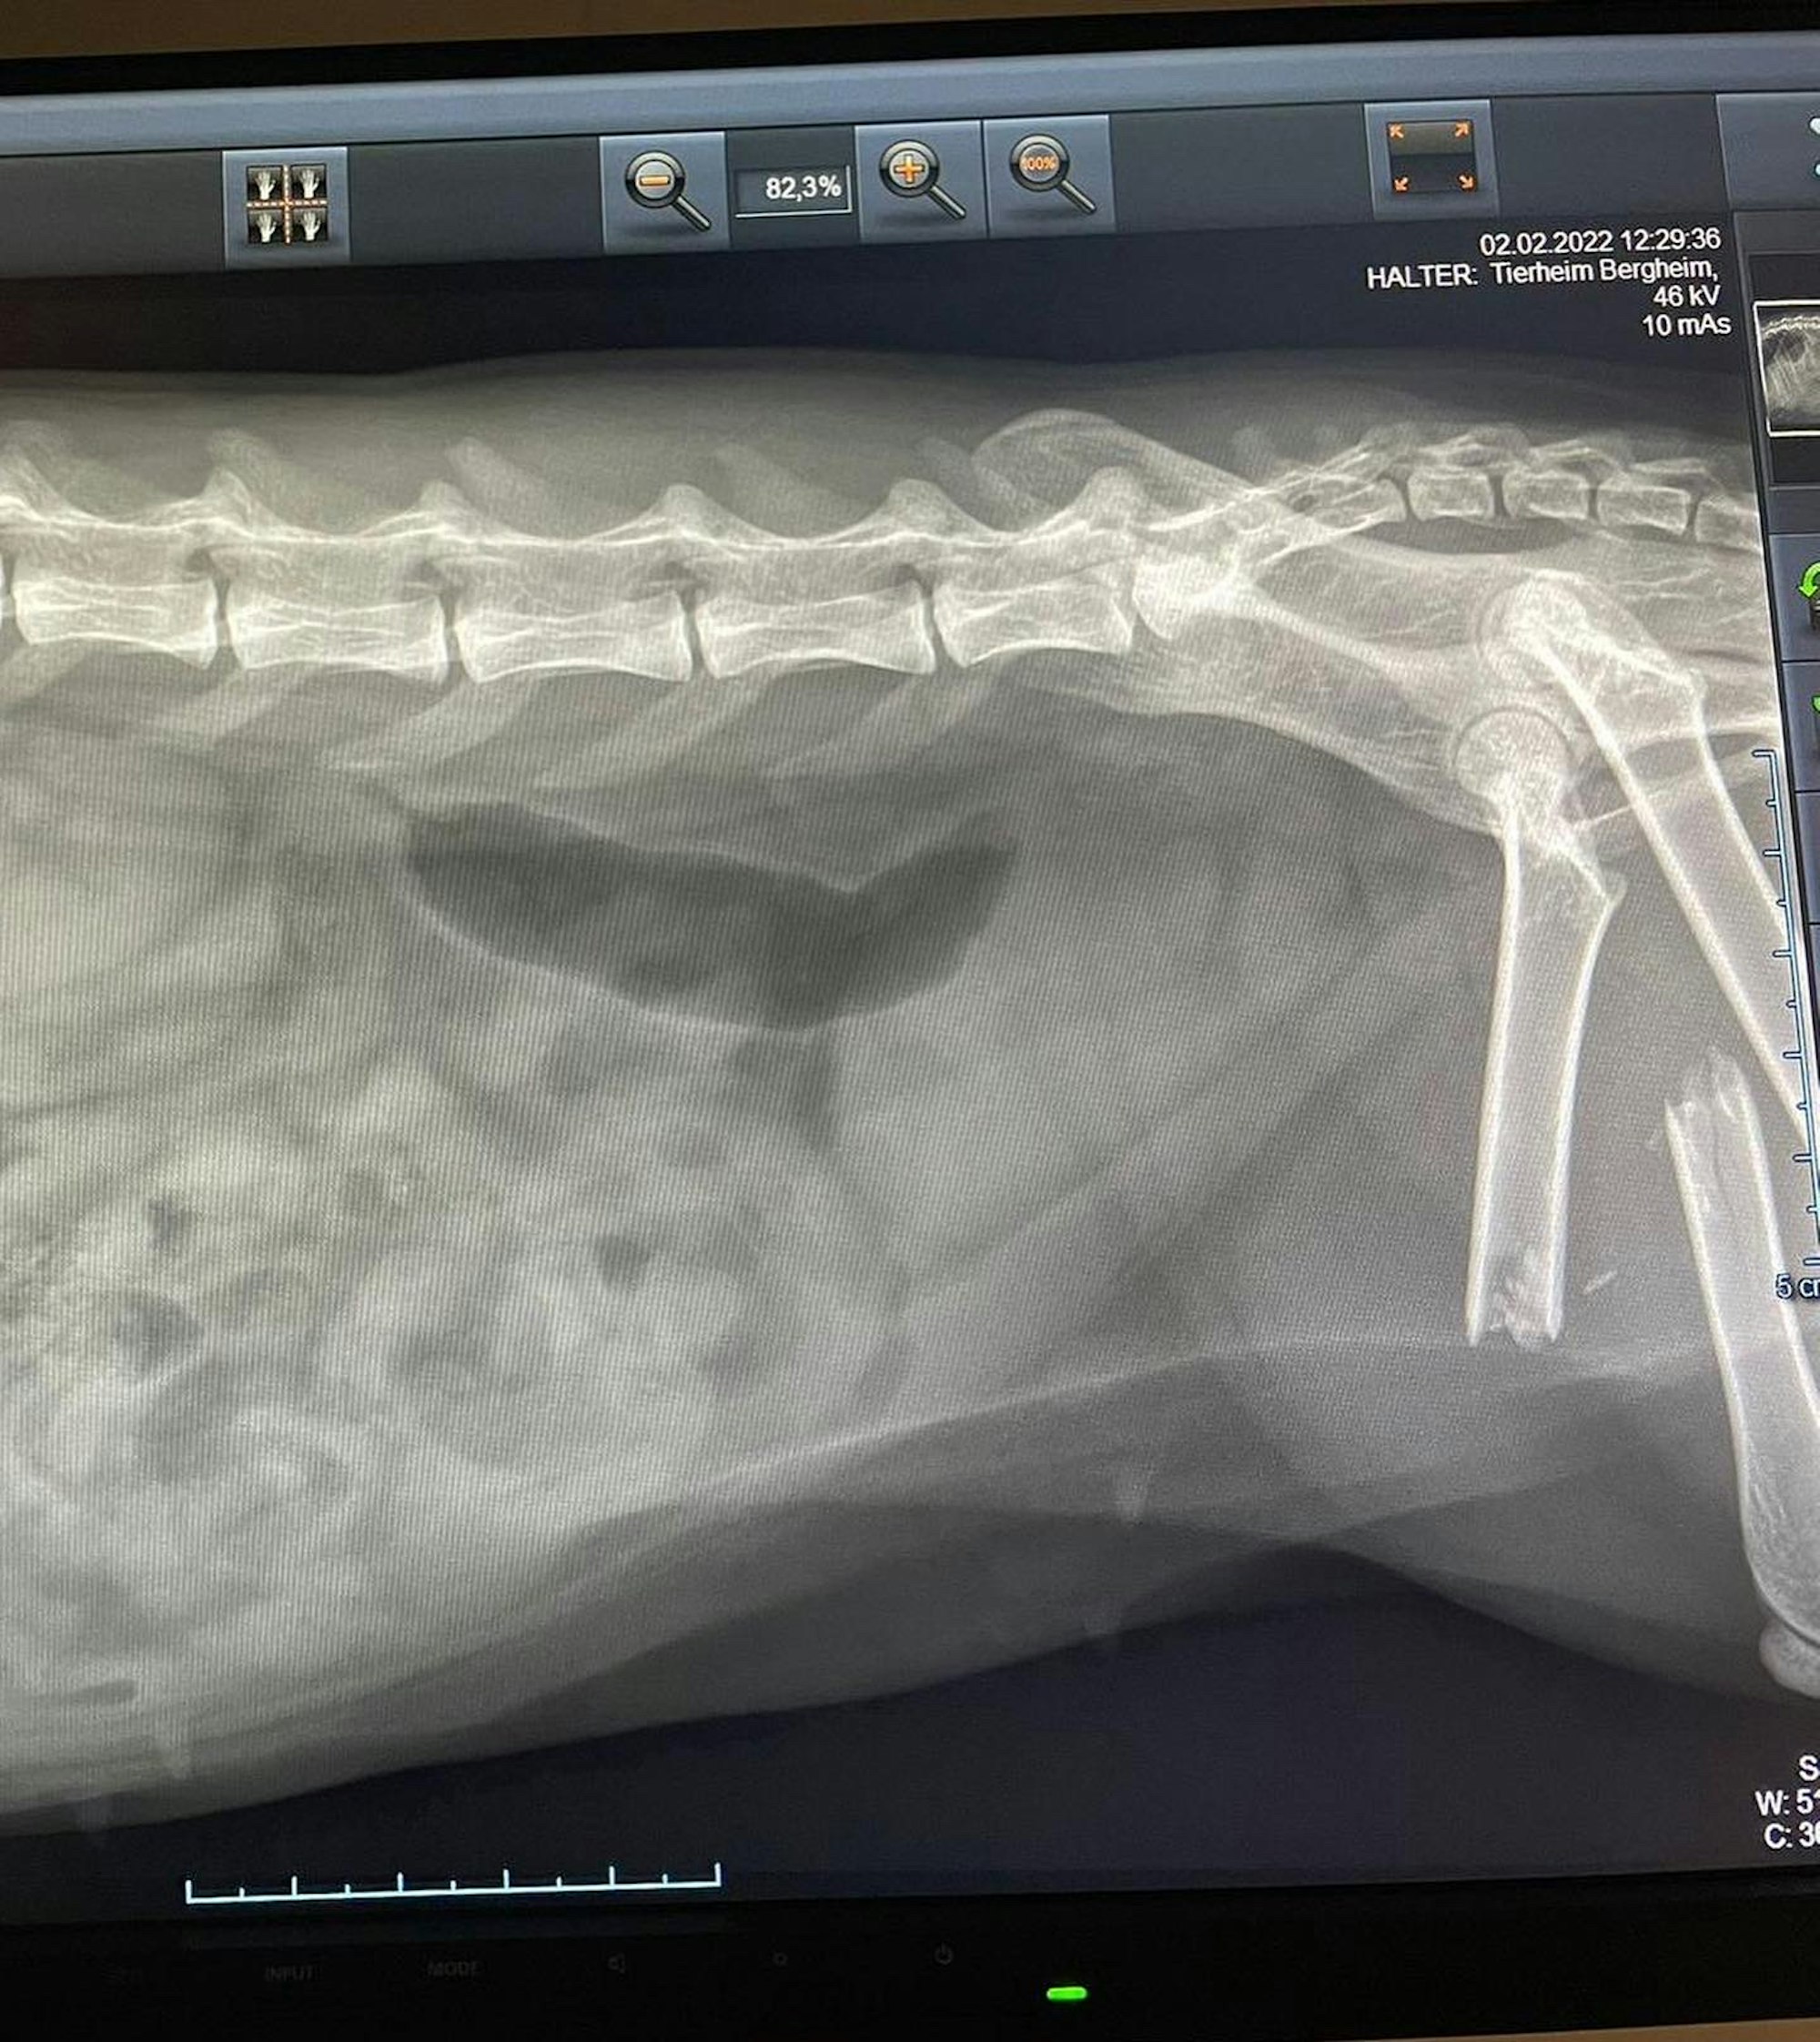

Vor einigen Tagen haben die Wehrleute das Tier am Straßenrand der Glescher Straße gefunden. Die Katze konnte kaum laufen, das Röntgenbild lieferte dann den Beweis: Der hintere, rechte Oberschenkelknochen war komplett durchgebrochen. In einer Klinik in Neuss wurde die Katze operiert.

Der hintere, rechte Oberschenkelknochen war komplett durchgebrochen.